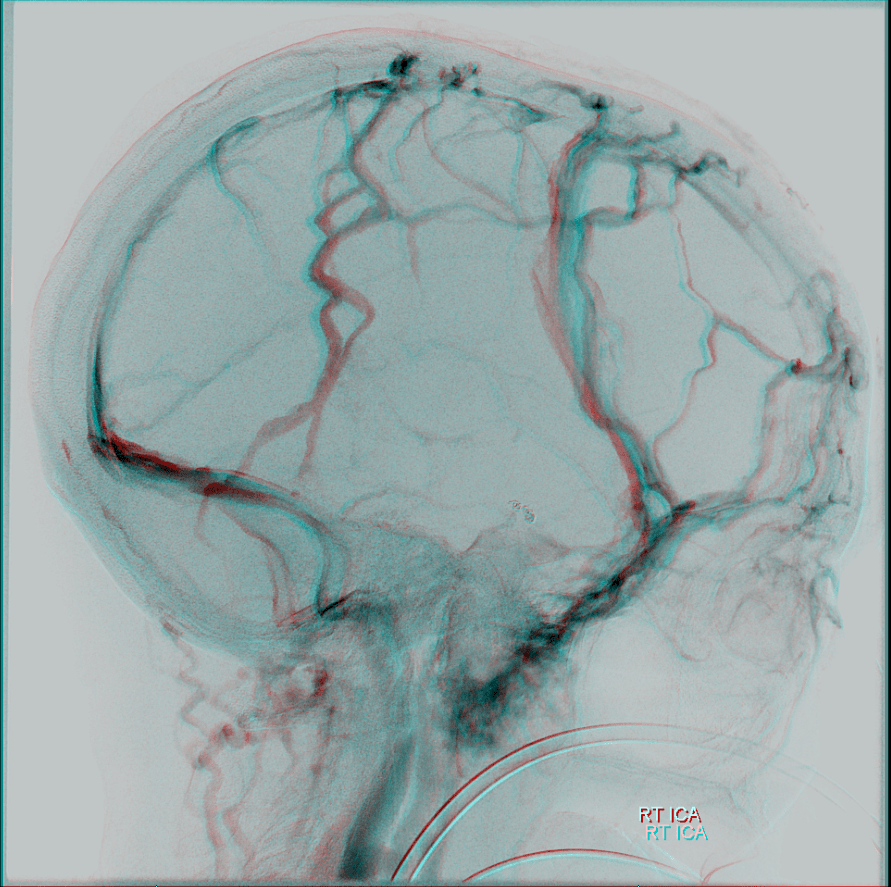

Web the diploic veins are located in the diploe, between the inner and outer tables of the bone of the calvarium. Web clival diploic veins are veins that travel through the body of the clivus connecting intracranial venous structures on the inner surface of the skull (e.g. These veins connect the intracranial and the extracranial venous. Web 1 definition the diploic veins are veins situated within the diploe of the calvaria. They change in size during growth from adolescence to. Web the diploic veins can serve as transit for infections from the scalp to the structures contained with. Web the diploic veins (dvs) are intraosseously formed, distinct venous networks that were first described in 1928. Although it is known that diploic veins frequently communicate with the dural venous sinuses, the role of diploic veins in patients with venous sinus invasion from. Web di·plo·ic vein [ta] one of the veins in the diploë of the cranial bones, connected with the cerebral sinuses by emissary veins; Web diploic veins are veins in the diploic space of the skull — the space between inner and outer tables.

These veins connect the intracranial and the extracranial venous. Neurosurgeons and plastic surgeons can be. Web diploic veins are veins in the diploic space of the skull — the space between inner and outer tables. Their walls are thin, and. The main diploic veins are the frontal, anterior. Web clival diploic veins are veins that travel through the body of the clivus connecting intracranial venous structures on the inner surface of the skull (e.g. Web the diploic veins (dvs) are intraosseously formed, distinct venous networks that were first described in 1928. Suggest a definition i agree herein to the cession of rights to my contribution in. Web the diploic veins are located in the diploe, between the inner and outer tables of the bone of the calvarium. There is no definition for this structure yet. They change in size during growth from adolescence to.